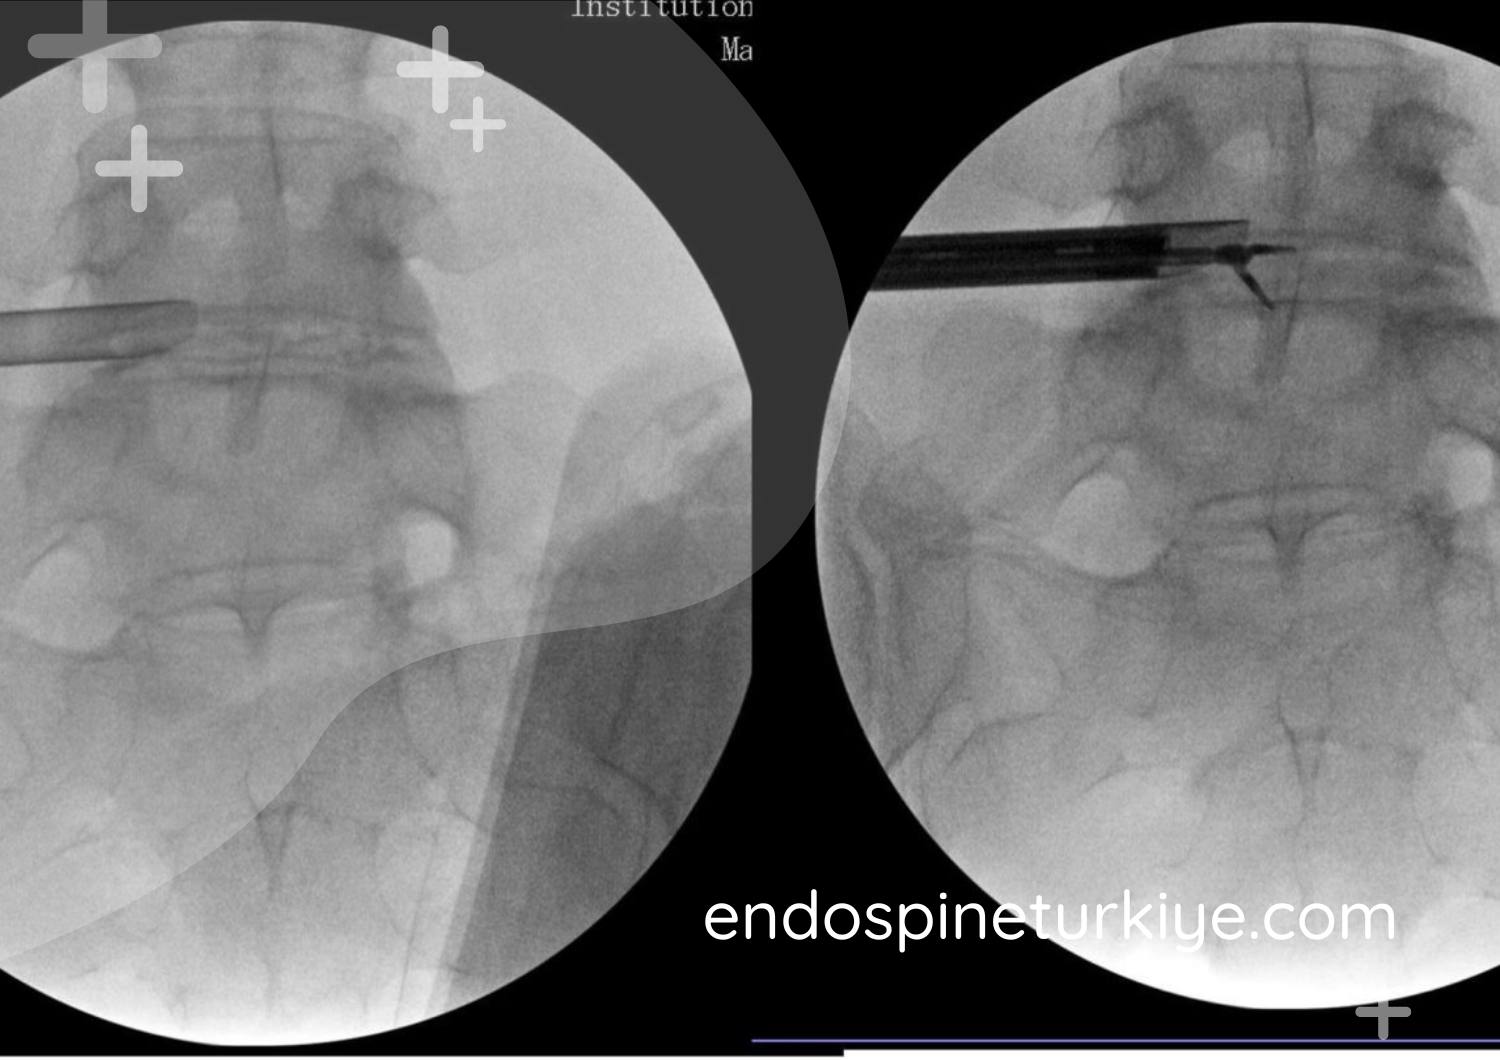

Endoskopik Cerrahi

6mm'lik açıklıktan endoskop konumlandırılır, HD görüntüleme altında fıtık materyali uzaklaştırılır.